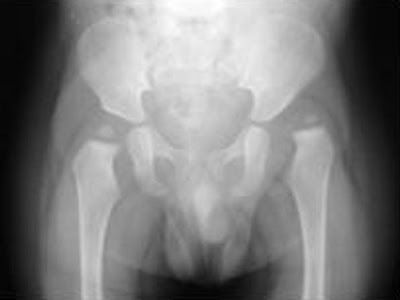

La cabeza no importa el tamaño ya que puede ser grande o pequeña pero siempre va estar deformada perdiendo su forma esférica aplanándose en sentido lateral con la cara que esta apoyada sobre el cotilo por lo tanto es muy frecuente que se generen lesiones por ello a la altura del cartílago diartrodial.

En el cotilo el techo es de una malformación displásica sin pared anterior, poco profunda y ha perdido su forma. En estos casos lo mejor es una intervención quirúrgica ya que es irreversible.